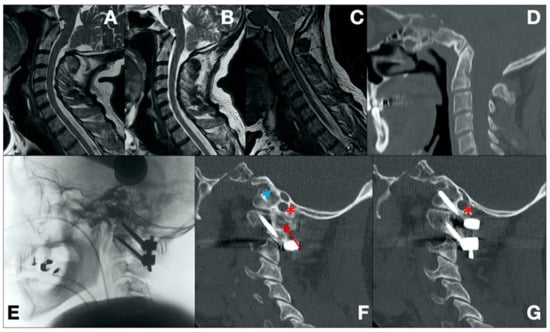

- Case 1 (Figure 1)

| 1 | 59/F | AA, BI | C0/C1–C2 (Laminar) + Bilateral cages | NA | 58 | 1 |